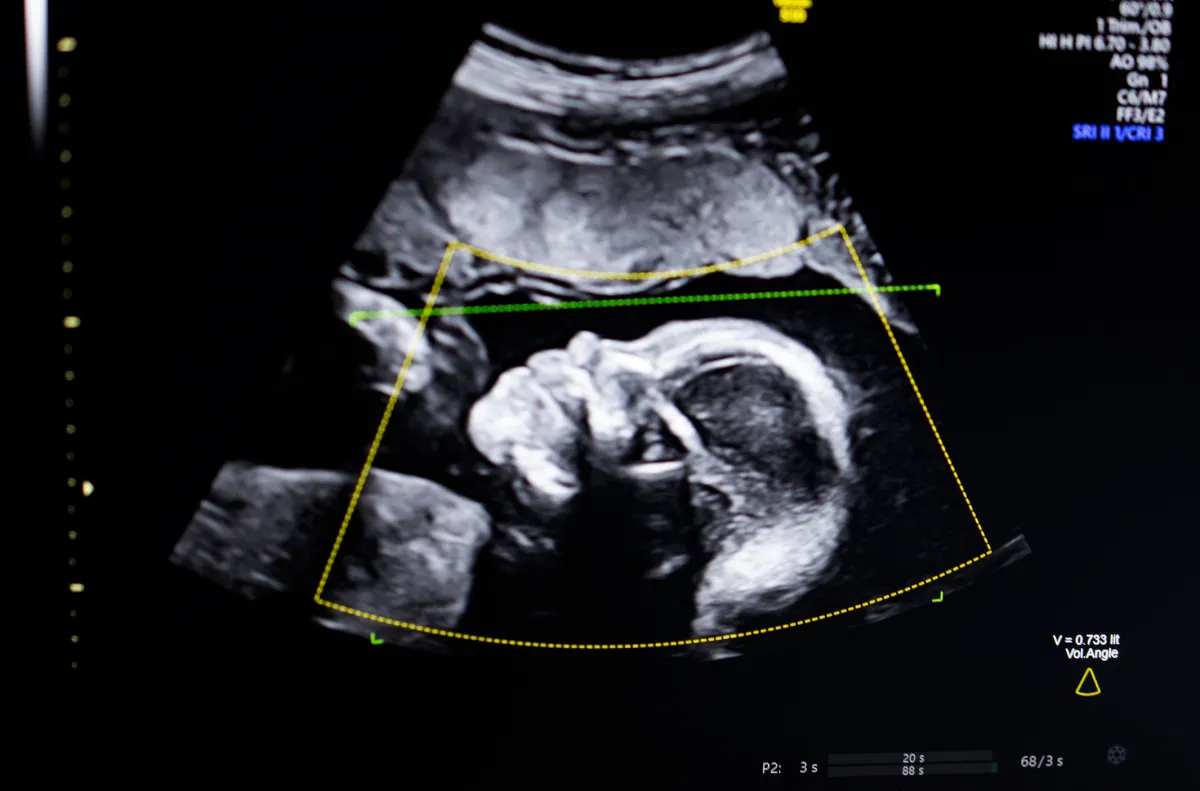

TechCrunch Disrupt Battlefield 2023 winner, Biotics AI, introduced on Monday that it has acquired FDA clearance for its AI software program that helps detect fetal abnormalities in ultrasound images.

The know-how makes use of pc imaginative and prescient AI “to assist fetal ultrasound high quality evaluation, anatomical completeness, automated reporting, and seamless integration into medical workflows,” Bustami instructed TechCrunch.

Bustami stated that the prenatal ultrasound has turn into the “cornerstone” of monitoring pregnancies, however its low-quality photos can result in misdiagnosis.

Bustami stated the toughest half was not constructing his AI fashions, which had been skilled on a various set of 11,000 ultrasounds, however guaranteeing the tech carried out reliably in the actual world, particularly on demographics with the very best threat for a tragic end result.